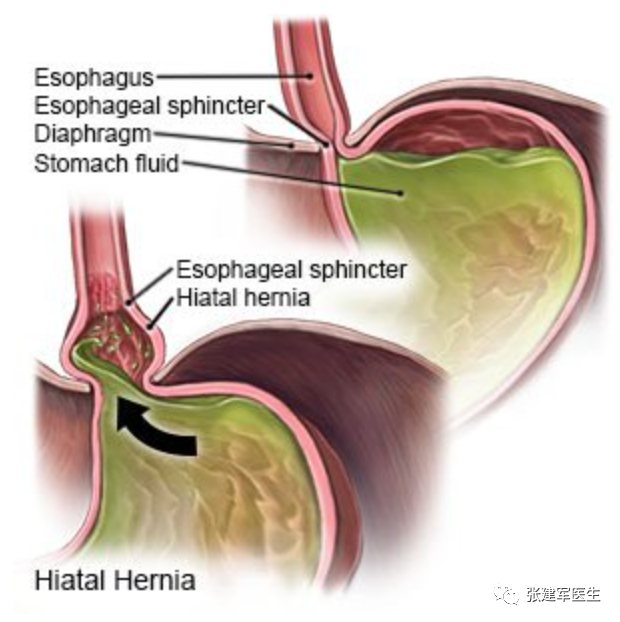

食管裂孔(Hiatus)是膈肌上的一个孔隙,食管通过该孔从胸部进入腹部。当胃的一部分通过膈食管裂孔进入胸腔,就发生食管裂孔疝(Hiatus herni),又称膈肌食管裂孔疝,简称裂孔疝。可导致胃食管返流或咽喉反流,其症状包括口腔酸味或胃灼热感。其他症状包括吞咽困难和胸痛。并发症可能包括缺铁性贫血,肠扭结或肠梗阻等。

食管裂孔疝的类型

食管裂孔疝主要有两种类型:滑动性食管裂孔疝和食管旁食管裂孔疝。大多数为滑动型食管裂孔疝,即1 型。其他三种类型均为食管旁疝。

Ⅰ型(滑动性食管裂孔疝):食管胃交界处(食管胃结合部)从腹部移位至胸部,约占 食管裂孔疝95% 的病例。

II型(食管旁疝或滚动性食管裂孔疝):胃食管结合部在膈肌下正常解剖位置,胃底或胃体通过胃食管裂孔疝入胸腔,胃底在食管胃结合部上方。

III型(混合型食管裂孔疝) – 它是 I 型和 II 型的组合,其特征是胃大弯和胃食管结合部均进入胸腔。

IV型食管裂孔疝 除了胃之外,腹腔内其它脏器如脾脏、部分结肠、网膜等也通过食管裂孔疝入胸腔。